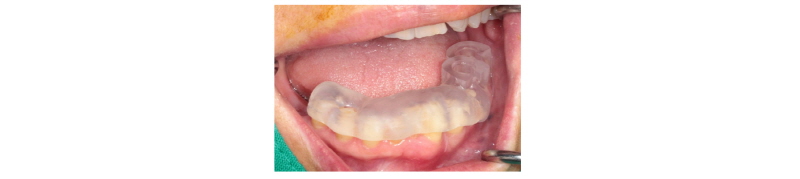

Fig. 26. Surgical guide positioned on mandible. |

Ju Whan Lee : Computer-guided Flapless Implant Surgery and Immediate Loading with Customized Restoration, Comparing and Reviewing Error of Guided Surgery. Implantology 2017 |

본 59세 여환은 양쪽 위, 아래 큰 어금니가 흔들리고 잇몸이 부었으며 왼쪽 아래 큰 어금니는 오랫동안 없었다는 주소로 본원에 내원하여 임상 및 방사선학적 검진 결과 아래와 같이 관찰되었다. #33 치아는 Mob (+++) Per (+)와 bone loss, #16, 26, 46 치아는 Mob (++/+++) Per (+)와 bone loss, #36, 37 치아는 missing 상태였다. 이에 #16, 26, 33, 46 치아는 hopeless teeth, #17, 36, 37, 47 치아는 missing teeth로 진단되었다(Fig. 19). #16, 26, 33, 46 치아는 발치 후, #i16, i17, i26, i33, i36, i37, i46, i47에 implant 식립과 #i16, i17, i26에 sinus lifting 및 #i33, i46, i47에 GBR을 계획하였다. #i36, i37은 flapless implant surgery 및 immediate loading을 계획하였다. #16, 26, 33, 46 치아를 발치하였고, 2개월 후에, 상, 하 rubber impression 채득 후, stone model 제작하였다. 또한 arch 전용 tray를 bite한 상태로(Fig. 20, 21) CBCT 촬영을 하였다(PHT-30LFO, VATECH). 이후 CBCT 영상과 alveolar ridge와 soft tissue model을 scanning한 영상(TRANSFORMER, Megagen)을 정합하였다. 새로운 영상을 바탕으로 #i36, i37 위치에 implant fixture 식립과 customized abutment와 provisional bridge를 design하였다(R2GATETM, Megagen, Fig. 22, 23). Design대로 3D printer (Perfactory Digital Dental Printer 3, EnvisionTEC) 통해 surgical guide를 제작하였고(Fig. 24) milling machine (TicamPro and WhitecamPro, Megagen)으로 customized abutment와 provisional bridge를 milling하였다(Fig. 28). 임플란트 수술은 5회에 걸쳐서 진행하기로 하였다. 첫 번째 수술일에는 #i36, i37 fixture 식립과 동시에 abutment 체결과 provisional bridge를 합착하였다(Fig. 25-27, 29). 이후, 1개월 후에 #i16, i17 fixture 식립과 lateral approach로써 sinus lifting을 시술하였다. 3개월 후에 #i36, i37에 최종 인상 채득하여 도재금관 수복을 하였다(Fig. 30, 31). 향후 남은 부위에 임플란트 수술 및 보철 진행 예정이다.